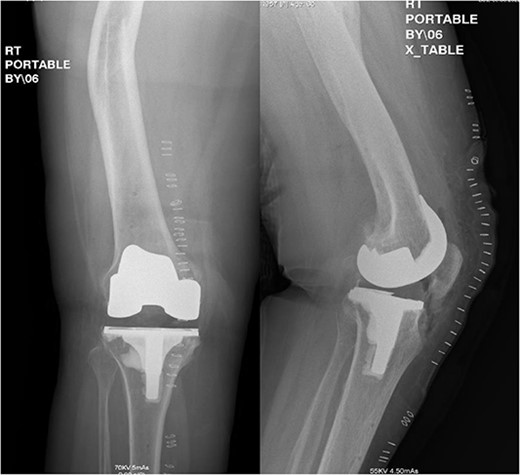

A 66-year-old woman with a history of right femoral shaft fracture, which was managed conservatively and resulted in malunion with right varus knee deformity. At the age of 54 years, she was diagnosed with osteoarthritis, and conservative treatment options, including weight reduction, non-steroidal anti-inflammatory medications, physiotherapy and intra-articular steroid injections, had been exhausted. Knee pain continued to worsen over the years, with negligible improvement in her symptoms. On physical examination, there was obvious varus deformity of the right knee, and significant restriction in the range of motion from full extension to 90° flexion. X-rays were requested, which revealed severe tri-compartmental knee osteoarthritis, a 3 cm medial shift of the right lower-limb mechanical axis, and 80° anatomical lateral distal femoral angle (aLDFA) and 96° mechanical lateral distal femoral angle (mLDFA) (Figs 1 and 2). The findings were discussed with the patient, who agreed to proceed with TKA. Given the complexity of this case with the femur deformity, the CORI Smith & Nephew surgical arthroplasty system was recommended as the surgical option that was suited to the patient’s specific bony anatomy and appropriate positioning of the components.

Preoperative anteroposterior standing bilateral lower extremity radiographs displaying long leg alignment and the right femur Varus deformity.

Preoperative anteroposterior, lateral and sunrise radiograph views displaying tri-compartmental osteoarthritis.